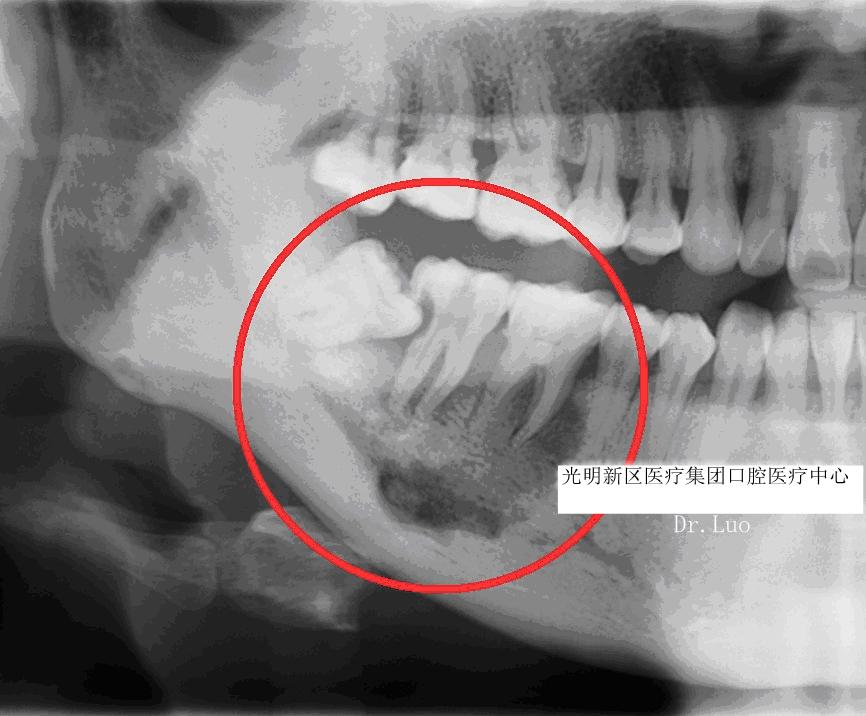

而“阻生”智齿是之那些由于邻牙、骨或软组织阻碍而只能部分萌出或完全不能萌出,且以后也不能萌出的第三磨牙。

那么阻生智齿有什么危害呢?

4)根、骨吸收:

由于智齿生长持续的压力压迫,造成邻近牙齿、骨质的吸收。可导致邻牙不适、疼痛甚至松动脱落。

5)牙源性囊肿、肿瘤:

长期的炎症、压迫周围组织可能导致颌骨囊肿、牙源性肿瘤的产生。不仅可能造成邻牙的松动脱落,还可能引起下颌神经的损伤、颌骨的病理性骨折,甚至有肿瘤后癌变的可能。

阻生智齿的罪过如此之多,引起的疾病如此棘手,所以面对阻生智齿,面对这个不定时的*弹炸**我们必须毫不手软,坚决予以铲除——尽快拔除。